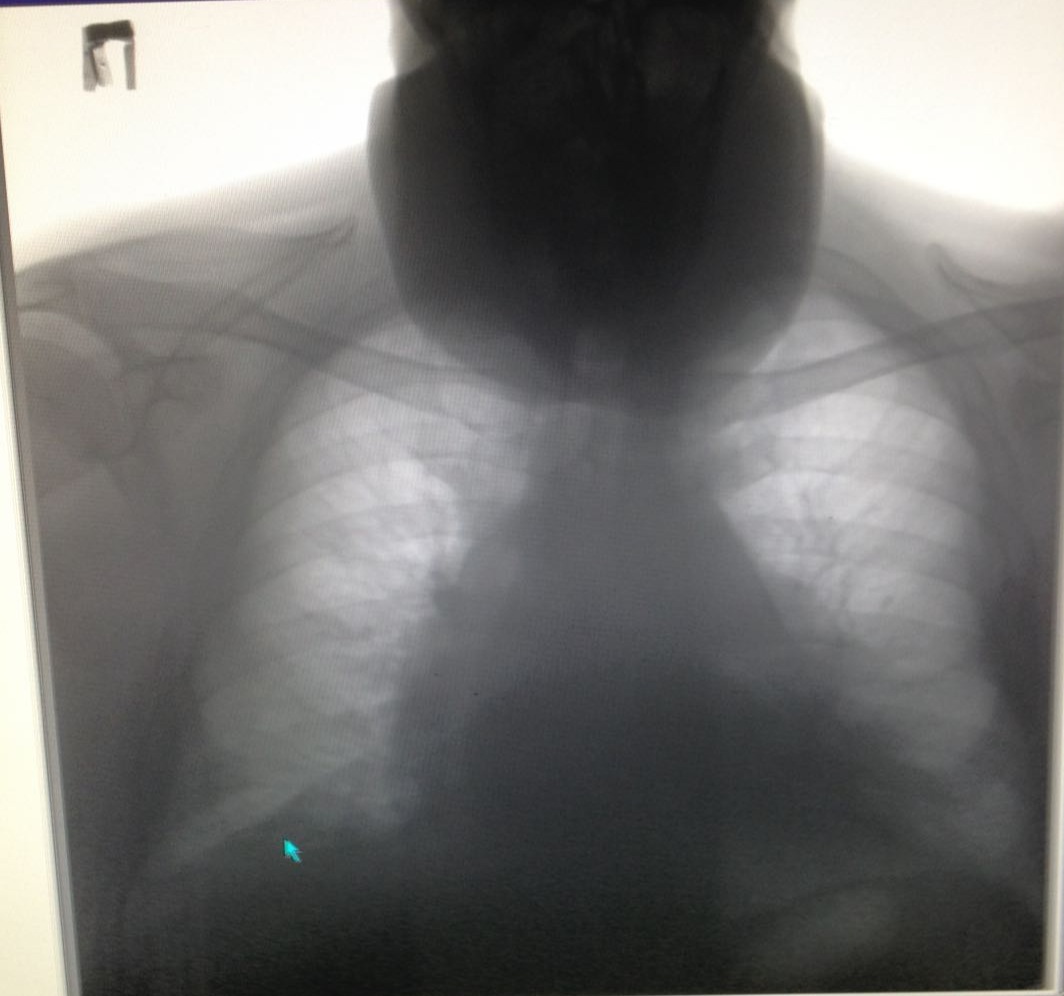

Зоб но на шее

Не обсуждалось

IMG_6161-.jpg